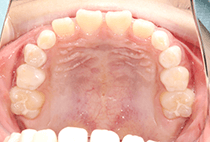

20代女性の患者さま。

八重歯の見た目が気になってご来院されましたが、実は顎の痛みや開口障害など、顎関節症の症状もありました。

そのため、かみ合わせと顎関節症の治療を同時に行ったにもかかわらず、2年間で治療が終了。

かみ合わせが整い咬筋の過緊張も改善しました。咬筋の肥大も治ってフェイスラインがすっきりしました。

最終的には美しい歯並びと、安定した痛みのないかみ合わせが実現しました。

八重歯が気になる

叢生、顎関節症、開口障害

しっかり前歯を下げるために、インプラントアンカーを使用してコントロールしました。

かみ合わせが整うと咬筋の過緊張が改善。

過緊張による筋肉肥大も改善しフェイスラインもすっきりしました。

治療前

治療後